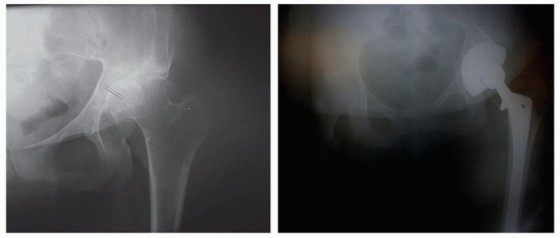

في مواجهة التحديات المتمثلة في نقص مخزون العظام في التجويف الحقي لمرضى DDH، ظهرت تقنية "ترقيع رأس الفخذ الذاتي" كحل مبتكر وفعال للغاية.

"ترقيع رأس الفخذ الذاتي" (Autogenous Femoral Head Graft) هو إجراء جراحي يستخدم جزءًا من رأس عظم الفخذ الخاص بالمريض، والذي يتم استئصاله عادةً كجزء من عملية استبدال مفصل الورك الكلي، لتعزيز التجويف الحقي. بدلاً من التخلص من رأس الفخذ المستأصل، يتم تشكيله ومعالجته ليتم استخدامه كطعم عظمي لملء العيوب أو تعميق التجويف الحقي الضحل.

لماذا هو ضروري في حالات DDH

في حالات DDH المتقدمة، غالبًا ما يكون التجويف الحقي (الحُق) غير مكتمل النمو، ضحلًا جدًا، أو يفتقر إلى الدعم العظمي الكافي لتثبيت الكوب الاصطناعي بشكل آمن. يؤدي هذا النقص في مخزون العظام إلى:

باستخدام ترقيع رأس الفخذ الذاتي، يتمكن الجراح من:

* تعميق وتوسيع التجويف الحقي: إنشاء تجويف عظمي طبيعي وعميق لاستقبال الكوب الاصطناعي.

* استعادة مخزون العظام: توفير دعم عظمي قوي وثابت للمفصل الاصطناعي.

* تصحيح مركز دوران الورك: إعادة المفصل إلى موقعه التشريحي الطبيعي، مما يصحح تفاوت طول الساقين ويحسن الميكانيكا الحيوية.